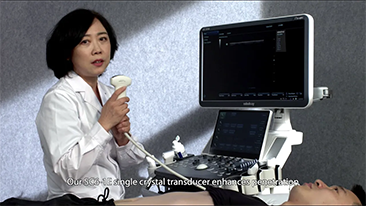

Algemene beeldvorming

Mindray Resona-oplossingen voor algemene beeldvorming helpen clinici bij het realiseren van nauwkeurigere en effici?ntere diagnose- en behandelingsresultaten door middel van sondes voor aparte toepassingen en effici?nte klinische toepassingstools.